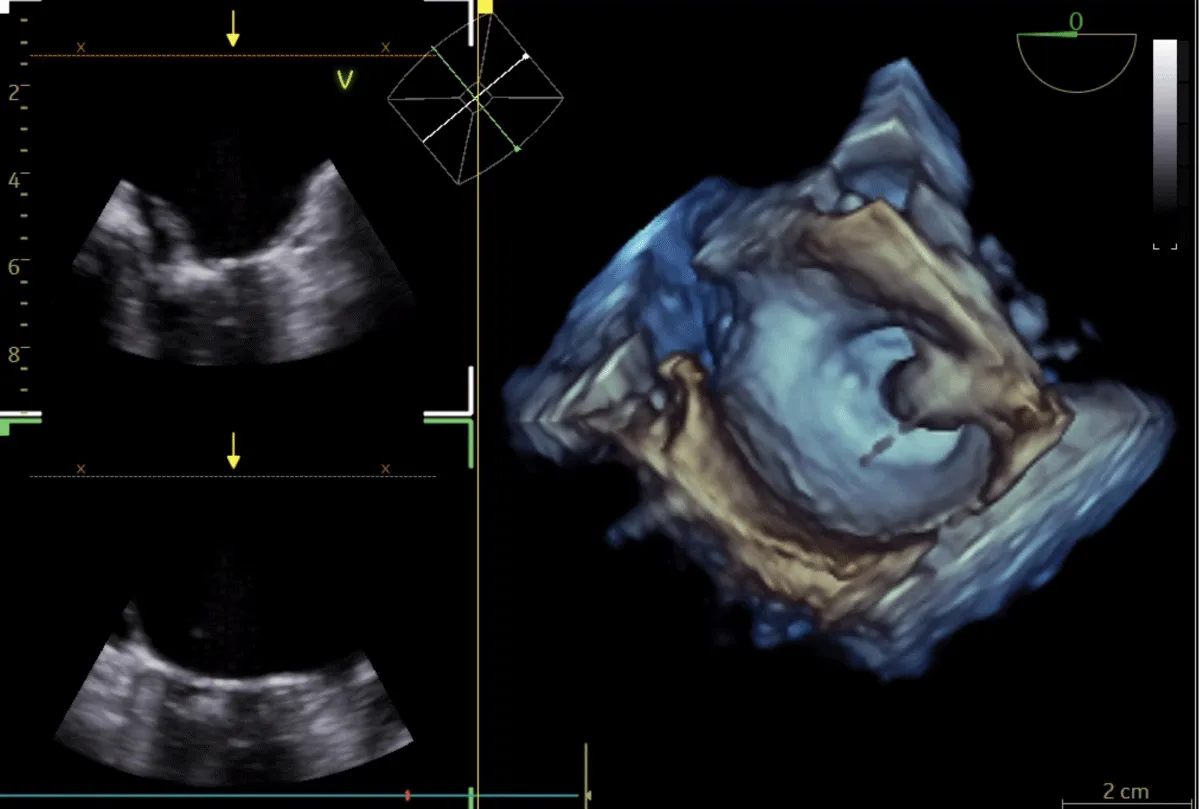

He was planned for double valve replacement (DVR), but the patient declined due to the high surgical risk. Therefore, he was considered for staged BMV and Transcatheter aortic valve replacement (TAVR). Pre-procedural planning was done for TAVR, and after ensuring the patency and adequacy of femoral vessels, he underwent a coronary angiogram (CAG), which showed normal coronaries. Following consent, the right femoral vein was accessed. A transseptal puncture was performed with a broken Brough needle, and the LA wire was parked. The MV was dilated with a 26 mm Inoue balloon (Figure 7), resulting in a reduction of the MV gradient from 24/10 mm Hg to 9/5 mm Hg and an increase in MV area from 0.9 cm2 to 1.6 cm2. There were no post-procedural complications. After 1 month, he underwent TAVI. Both right and left femoral artery access was obtained. Following pre-dilatation of the AV with an 18 mm balloon, TAVR was performed using a 26 mm balloon-expandable valve (Myval, Meril Lifesciences, Vapi, Gujarat, India) (Figure 8) (Video 3), followed by post-dilatation under accelerated right ventricular pacing (180 bpm). ECHO and final aortography showed no paravalvular leakage after device release (Figure 9).

Figure 8: Fluoroscopic image of Balloon dilatation of the aortic valve (A) followed by aortic valve implantation (B) under right ventricular pacing.

Figure 9: Fluoroscopic image of aortic valve implantation without coronary compression after (A) and before the deployment (B).

Post-TAVR, the AV gradient was reduced from 98 →10 mm Hg. No procedural or post-procedural complications occurred. The hospital course was uncomplicated, and the patient was discharged after 4 days.